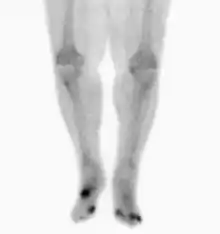

Osteomyelitis in both feet as seen on bone scan

Nuclear medicine scans can be a helpful adjunct to MRI in patients who have metallic hardware that limits or prevents effective magnetic resonance. Generally a triple phase technetium 99 based scan will show increased uptake on all three phases. Gallium scans are 100% sensitive for osteomyelitis but not specific, and may be helpful in patients with metallic prostheses. Combined WBC imaging with marrow studies have 90% accuracy in diagnosing osteomyelitis.[22]